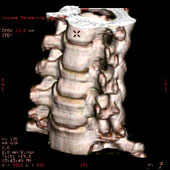

All of our latest generation CT machines have multiple detectors and even greater computer speed. Our CT scanners can image a patient with continuous table movement and multiple simultaneous spiral cuts covering the body in a matter of seconds